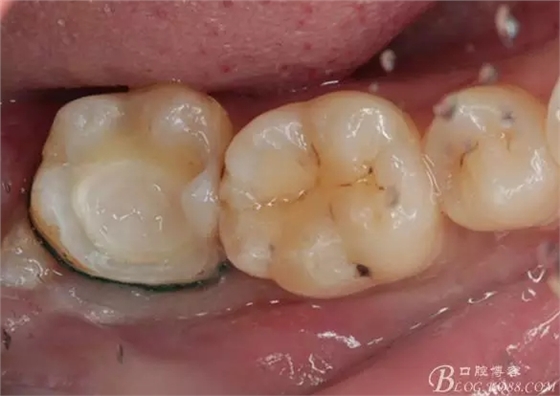

一周后復(fù)診,37臨時(shí)充填物完好。去除臨時(shí)充填物,清潔基牙,試戴嵌體,就位良好,邊緣密合。取下嵌體,常規(guī)處理,9.5%HF處理20S,沖洗一分鐘,95%酒精蕩洗5分鐘?;劳磕?7%的磷酸凝膠,釉質(zhì)區(qū)域酸蝕30S,本質(zhì)區(qū)域15S。粘固用的是3M第八代粘接劑套裝,照說明書逐步操作。最終固化時(shí)涂滿阻氧劑,每個(gè)牙面最少光照30S,光固化燈用漸強(qiáng)模式。常規(guī)調(diào)合,配合硅膠尖套裝拋光。術(shù)后常規(guī)醫(yī)囑,不適隨診。

回訪:術(shù)后一周電話回訪無異常。

④嵌體顏色與基牙的差異也是一遺憾。